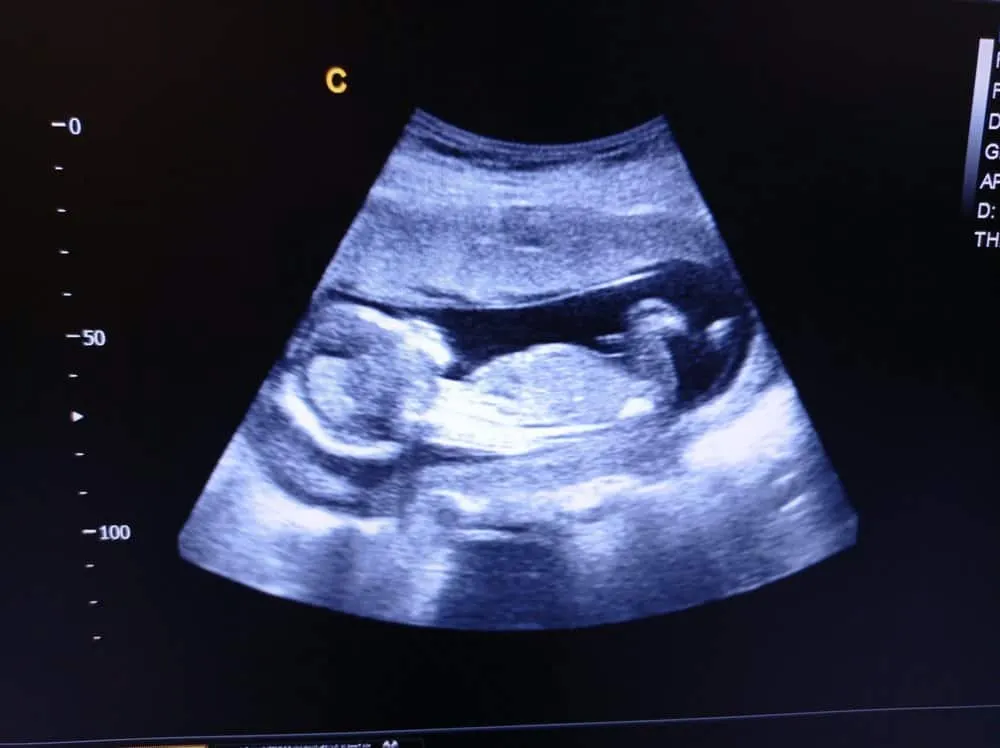

Để tính thông số này, bác sĩ sẽ siêu âm bụng của sản phụ. AC được đo theo mặt phẳng ngang tại gan của thai nhi, với điều kiện:

- Các nhánh tĩnh mạch rốn đổ vào gan hợp với xoang tĩnh mạch cửa trái ở vị trí giữa bụng

- Trong mặt phẳng này, tĩnh mạch rốn và tĩnh mạch cửa tạo thành hình chữ J

- Dạ dày được nhìn thấy ở bên trái của bụng thai nhi

- Bụng hình tròn thay vì hình bầu dục, vì hình bầu dục tạo ra vết cắt xiên dẫn đến ước tính sai về kích thước.

Những cơ quan này cần được xác định khi mẹ mang thai được 18-20 tuần. Khi đo AC, một đường đứt nét hình elip ảo sẽ hiện trong màn hình siêu âm, dọc theo bề mặt da bên ngoài bụng em bé, không sâu vào trong da bụng để tránh lỗi đo AC quá nhỏ. Độ dài của đường elip là chu vi vòng bụng thai nhi. Lưu ý, AC không được đo khi vùng bụng đã được nong rộng hay hóp lại. Bụng của thai nhi có thể thay đổi hình dạng do: